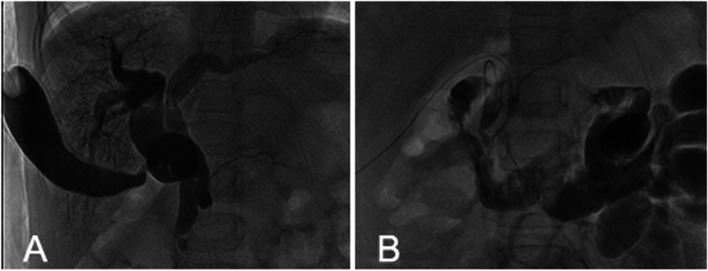

The patient is a 5-year-old Asian girl who had history of repeated abdominal pain for 4 days and aggravated for 1 day. Abdominal ultrasonography suggested dilatation of common bile duct with cholangitis, cholecystitis and abdominal effusion. Magnetic resonance cholangiopancreatography (MRCP) showed a common bile duct diaphragm which meant common bile duct duplication, with congenital biliary dilatation and cholelithiasis (Fig. 1). Symptomatic treatment including fasting, anti-infection, spasmolysis, and fluid rehydration was given. The temperature of the child was stable, and there were no obvious contraindications for surgery before operation. The patient underwent cholecystectomy and biliary tract plasty and Roux-en-y common bile duct jejunostomy and abdominal cavity irrigation and drainage under general anesthesia. Intraoperative cholangiography showed both distal openings into the duodenum and converged with the pancreatic duct (Fig. 2 A). The dilated sac wall of the common bile duct was partially removed, and the septum between the left and right hepatic ducts was excised and sutured to form a regular common bile duct. Intraoperative cholangiography(IOC) after repair showed that the morphology and drainage of common bile duct was normal, and large amounts of contrast medium entered the duodenum and jejunum(Fig. 2 B).The postoperative recovery of the child was good. Preoperative MRCP and IOC were shown in Figs. 1 and 2.